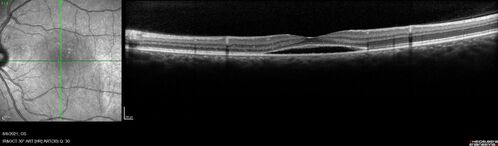

Central Serous Chorioretinopathy - Expanding hot spot - photodynamic laser

35 year old man with acute central serous chorioretinopathy.  The fluid got better then worse and the patient was treated with full strength juxtafoveal PDT and then got better.